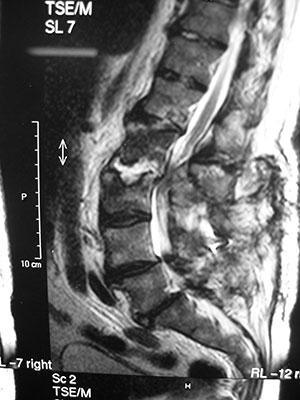

A apresentação clinica da discite pós operatória consiste em um período de melhora da dor seguido por um período de piora progressiva da dor lombar com ou sem irradiação de caráter radicular. A dor pode ser de grande proporção sem que a ferida operatória apresente qualquer sinal de infecção. A integridade neurológica esta mantida. A presença de qualquer alteração neurológica deve levantar suspeita de um abcesso epidural ou alguma outra complicação associada. Os exames laboratoriais auxiliam o diagnóstico e as provas inflamatórias como VHS e PCR estão elevadas. A RNM é o exame de imagem de escolha. Imagens hipointensas em T1 e hiperintensas em T2 são características e estão presentes 3 a 5 dias após o inicio da infecção. (figura 1)

Figura 1 - RNM de espondilodiscite pós operatória

A ressonância magnética é sem dúvida o melhor exame de imagem disponível. Ela tem uma sensibilidade de 96% e uma sensitividade de 93% para infecções piogênicas. Mesmo assim, no período pós operatório recente, é muito difícil diferenciar alterações infecciosas das alterações decorrentes do procedimento cirúrgico. A utilização de gadolíneo como meio de contraste auxilia na diferenciação dessas alterações. Alguns aspectos podem ser citados como característicos de infecções pós operatórias: áreas confluentes no corpo vertebral e espaço discal, hipointensas em T1 e hiperintensas em T2. Perda de distinção precisa entre os tecidos das vértebras e espaço discal adjacente e disco de aparência anormal.